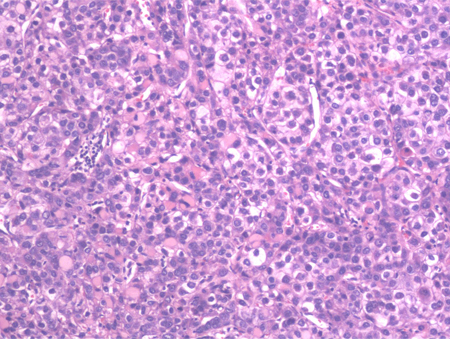

High-power view of hematoxylin and eosin stained section of a well-differentiated HCC. Predominantly a solid pattern of growth with some nesting of malignant cells, separated by compressed sinusoids; some cells have clearing of the cytoplasm